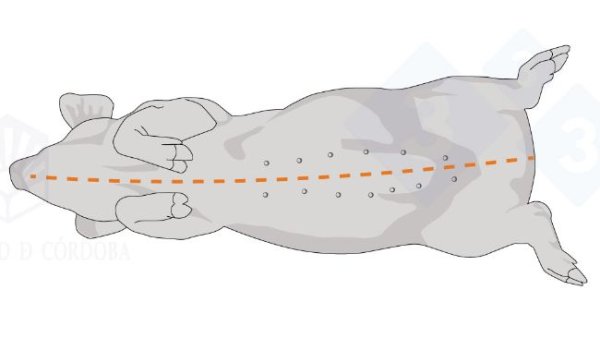

In the first two installments, we covered necropsy in lateral decubitus. In this third installment, we will look at necropsy in the supine position

In this second installment, we cover extracting the tongue, trachea, lungs, and heart in one piece. We will extract the organs of the abdominal cavity, both the digestive system and the urinary and genital tracts. In the head, we will access the nasal turbinates, brain, and cerebellum.